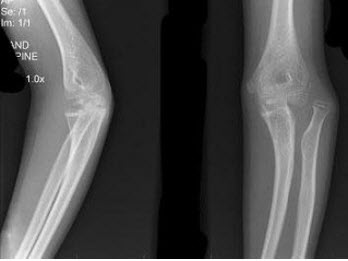

C.焦-物距增大,模糊度增大

209、单项选择题

男,12岁,右前臂外伤后入院。结合图像,正确的诊断是()

A.Colles骨折

B.孟氏骨折

C.青枝骨折

D.Smith骨折

E.桡骨小头脱位

B.可单骨或多骨发病

115、单项选择题

男,15岁,畏寒,高热2周,摄片如图所示,下列描述正确的是()

A.骨质广泛性溶骨性破坏

B.少许骨质增生硬化

C.大量层状骨膜增生

D.以上描述均正确

E.以上描述均不正确